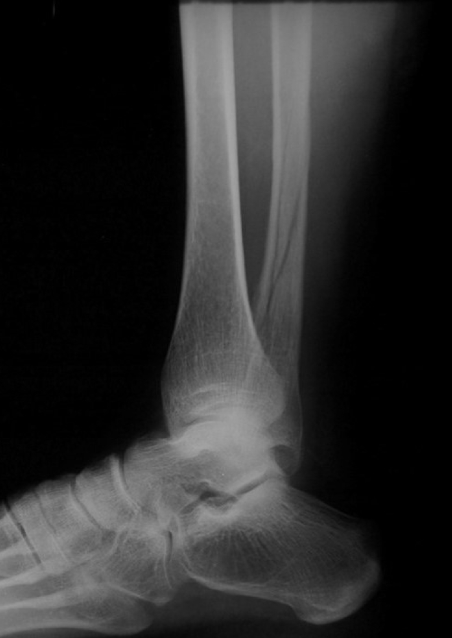

Q

Stress Fracture

A

Stress fracture –

gradually develops

from multiple

repetitions of force